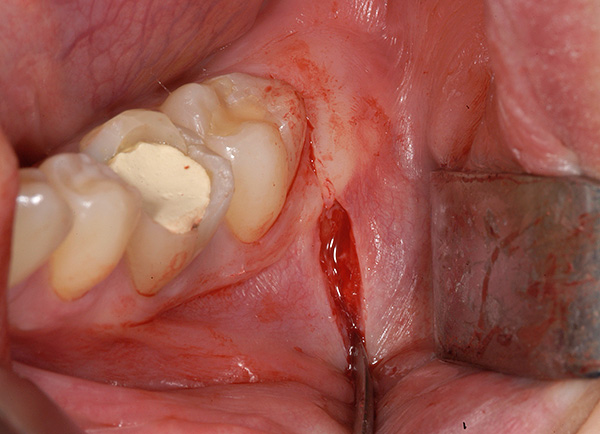

- Creazione dell'accesso al dente retinato (incisione della gomma con un bisturi, rimozione del tessuto osseo con taglierine con raffreddamento. In alcune cliniche possono utilizzare un bisturi laser);